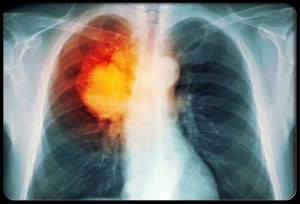

Whether or not a woman smokes may have a decisive impact on her breast cancer outcome. This is the case in the years preceding menopause, write Japanese researchers in “Cancer Science”.

Researchers from Tohoku University Graduate School of Medicine in Sendai analysed data from 848 women with breast cancer who were followed for an average of 6.7 years. Premenopausal women who had smoked for more than 21.5 years had a 3.1 times higher risk of dying from any cause and a 3.4 times higher risk of dying from breast cancer.

This effect was especially relevant in carcinomas that were both oestrogen and progesterone-positive. This association was not found in postmenopausal patients.